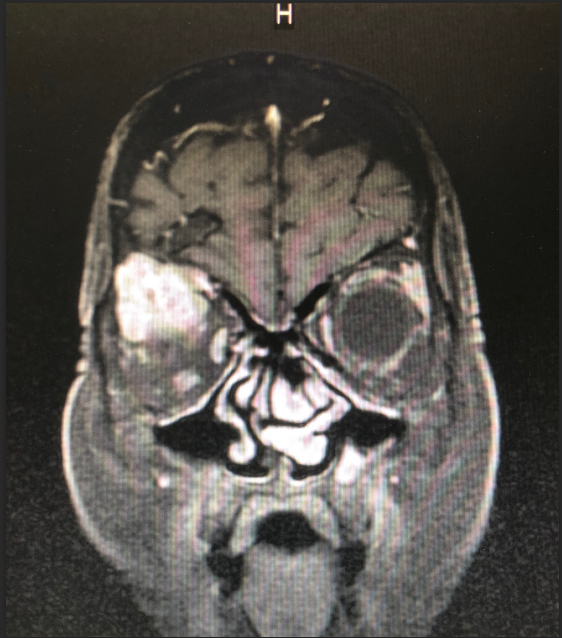

患者王女士,79岁,女性,2周前出现右眼疼痛,眼球突出,随后眼痛逐步加重,右眼视力急剧下降。在当地医院被诊断为眼眶内肿瘤,需手术治疗。但因患者眼眶肿瘤突破眼眶,向颅内生长,手术难度大。患者先后辗转多家医院眼科均无功而返。患者右眼疼痛难忍,最终选择到21点游戏攻略站 寻求最后的帮助。

21点游戏攻略站 神经外科团队接诊后对患者进行了全面检查,诊断为右眼眶肿瘤。因患者肿瘤向颅内生长,颅底及眼眶骨质已完全破坏,传统的手术方式不仅创伤大,更可能因为颅底结构无法完全重建导致患者脑脊液漏,引起颅内感染。神经外科联合眼科进行了手术方式的讨论,根据术中可能出现的各种情况其制定了详细的治疗方案,认真完善术前准备后,于2018年12月24日成功为其开展“完整切除颅内外沟通瘤并颅底眼眶重建修复手术”,手术过程非常顺利,术后患者无视神经损伤,视力较术前明显改善。目前患者已康复出院。